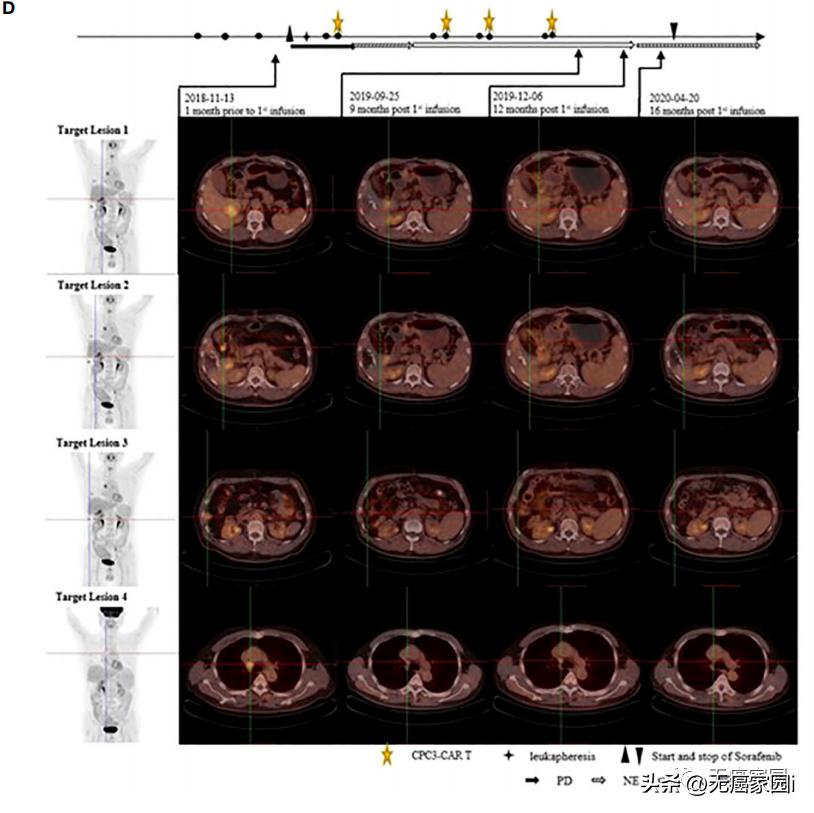

在第12个月时,4号靶病变的术后病理图像

(图像显示大面积凝固斑块坏死、外周纤维化、慢性炎性细胞浸润、无明显肿瘤残留,表明抗肿瘤治疗后有反应)

靶病变PET-CT图像

(患者在基线时接受PET-CT检查,首次输注后6、9、12、16个月。1号、2号和3号靶病变在第12个月消失,而4号靶病变病变不活跃,在抗肿瘤治疗后被认为是非特异性摄取)

CT011联合索拉非尼治疗耐受性良好。 患者从第3个月开始达到部分缓解(PR), 并 在第一个 CT011 输注周期后的第12个月达到完全缓解 。 肿瘤超过36个月没有进展,在第一次输注后保持完全缓解状态超过24个月。

据悉,这是CAR-T细胞与酪氨酸激酶*制剂抑**联合治疗后报告的首个完全缓解病例。临床结果表明, GPC3 CAR-T细胞与索拉非尼的联合治疗,可能成为治疗GPC3表达阳性的晚期肝细胞癌患者的一种有前景的疗法。